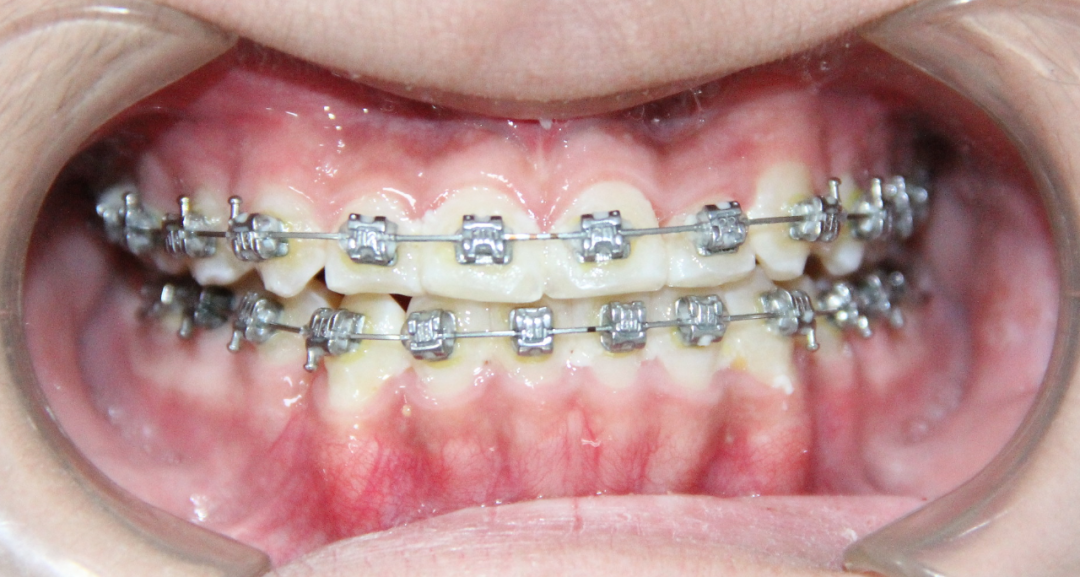

病例2

治疗前

治疗后